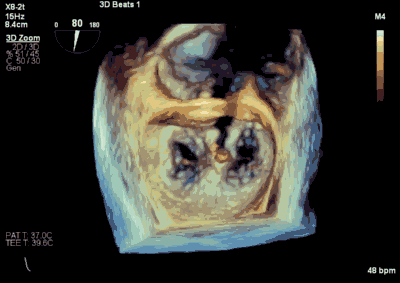

患者为66岁老年男性,4个月余前因“急性心肌梗死合并二尖瓣后叶腱索断裂”出现心源性休克,在IABP支持下仍反复发作左心心力衰竭,经过急诊血运重建联合优化药物治疗后症状好转,但术后多次发作严重左心心力衰竭,超声心动图评估二尖瓣反流急性增加至极重度,左房、左室显著扩大。此次主诉“反复胸闷、气促4月余”入院。诊断:心脏瓣膜病 二尖瓣脱垂伴重度关闭不全 二尖瓣后叶腱索断裂 心功能IV级(NYHA分级) 。术前经胸超声心动图示:全心扩大,二尖瓣后叶脱垂、腱索断裂合并重度关闭不全(DMR 4+)。心脏测值:LA 45mm LVD 55mm EF% 61% PASP 82mmHg。经食管超声心动图示:二尖瓣环左右径33mm,反流束缩流颈宽度为5.5mm,EROA 0.67cm2(PISA),舒张期二尖瓣口平均跨瓣压差5mmHg。

▲ 术前超声检查显示重度二尖瓣反流